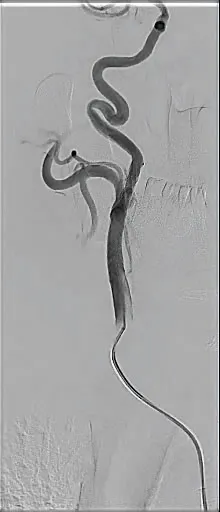

PATIENT PRESENTATION

A man in his early 60s with prior carotid endarterectomy (CEA) followed by interposition common carotid artery (CCA)–to–internal carotid artery (ICA) bypass for recurrent disease presented. Despite smoking cessation initiatives and optimal drug therapy, the patient continued tobacco use and developed progressive severe restenosis within the bypass conduit several years later, which was identified on surveillance duplex ultrasound. The distal anastomosis demonstrated high-grade restenosis > 80% (Figure 1A), and the bypass developed intraluminal thickening suggestive of soft heterogeneous plaque morphology on ultrasound (Figure 1B).

Figure 1. Longitudinal view ultrasound of the distal anastomosis at the ICA bypass demonstrating severe focal plaque burden (A). Axial view ultrasound of the proximal CCA at the level of the clavicle with heterogeneous intimal thickening (B).

Given the hostile operative field, redo open surgery carried increased risk for cranial nerve injury. Transcarotid artery revascularization (TCAR) was evaluated; however, circumferential plaque burden extending into the mid-CCA limited safe direct carotid access. The decision was therefore made to proceed with transfemoral carotid artery stenting (TFCAS) using distal embolic protection.

PROCEDURAL OVERVIEW

After ultrasound-guided transfemoral access, the patient was systemically heparinized. An aortic arch angiogram demonstrated a bovine, type II arch configuration. The CCA was selectively cannulated using a Van Schie 4 catheter (Cook Medical) and Glidewire® (Terumo Interventional Systems). Angiography confirmed a critical focal stenosis at the distal anastomosis of the bypass graft (Figure 2A). For enhanced stability, a 7-F Destination™ sheath (Terumo Interventional Systems) was advanced into the proximal CCA. A distal filter wire was then carefully navigated across the lesion and deployed in the distal ICA. A 10- X 20-mm Roadsaver™ dual-layer micromesh carotid stent (Terumo Interventional Systems) was advanced and deployed across the anastomotic stenosis. Postdilation was performed using a 5- X 40-mm angioplasty balloon to optimize luminal expansion and stent apposition. Completion angiography demonstrated an excellent result, with no residual stenosis, preserved distal flow, and no angiographic evidence of embolization (Figure 2B). The filter was retrieved and was free of visible debris, and the patient experienced no periprocedural neurologic events.

Figure 2. Selective angiography of the left carotid artery showing a focal severe luminal stenosis > 80% (A). Completion angiography post Terumo Roadsaver carotid stent demonstrating no residual stenosis (B).